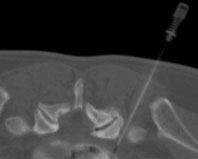

Injektion Facettengelenk Lendenwirbelsäule (Spritze in das kleine Wirbelgelenk unter CT-Kontrolle)

Nadelspitze exakt im Gelenkspalt des kleinen Wirbelgelenkes zwischen 5. Lendenwirbelkörper und Kreuzbein

Nach Injektion von Kortison, Lokalanästhetikum und Kontrastmittel in das kleine Wirbelgelenk, Verteilung des Medikaments im Gelenkspalt (wegen altersbedingten Löchern in der Gelenkkapsel) auch epidural